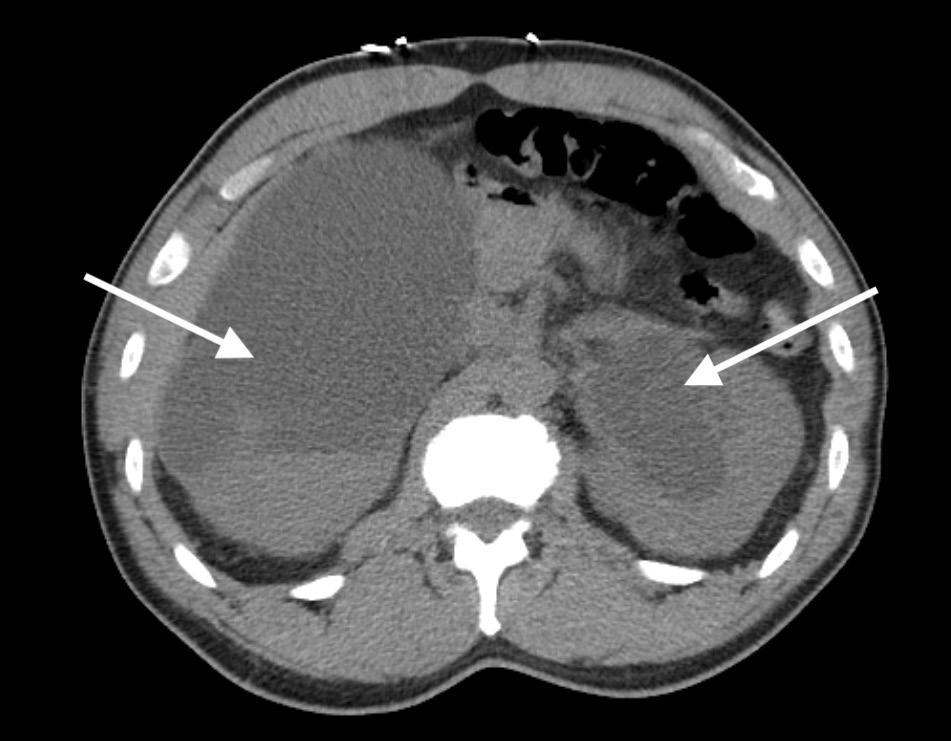

Given these findings, the patient was suspected to be in acute respiratory failure due to severe bronchiolitis. As the patient presented early at the onset of the coronavirus disease 2019 (COVID-19) pandemic, COVID-19 remained high on the differential, given little was known regarding its effects on infants. Oxygen was administered via non-rebreather (NRB) mask with broad spectrum antibiotics and intravenous fluids (IVF) due to concern for sepsis. His labs were notable for white blood cell count of 10.6 x 103 per millimeter (mm3) (reference range: 5x103 - 10x103 mm3) with a lymphocytic predominance; hemoglobin 20.4 grams (g) per deciliter (dL) (14-17 g/dL); creatinine of 0.4 milligrams (mg)/dL (0-0.5 mg/ dL); and a lactate of 12.5 millimoles per liter (mmol/L) (0-4 mmol/L). A COVID-19 polymerase chain reaction test was negative. Chest radiograph was interpreted by the emergency physician as technically limited due to rotation with diffuse prominent interstitial markings concerning for viral pneumonia (Image 1).

Addepalli et al. Point-of-care Ultrasound Diagnosis of Tetralogy of Fallot Causing Cyanosis: A Case Report Image 1. Portable anteroposterior chest radiograph showing no focal infiltrate and limited due to patient rotation.